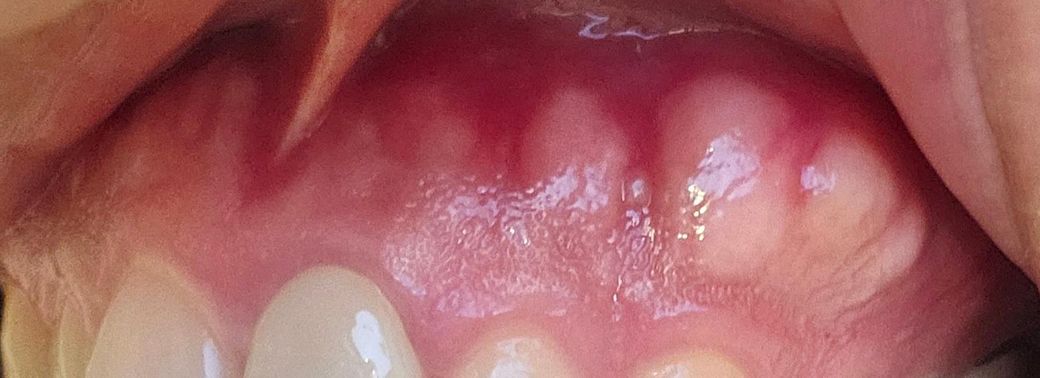

잇몸이 튀어나오는데 병인지 궁금해요

하얗게 보이는 부분을 만져보면 치아 뿌리같아요

원래 이랬는지를 모르겠는데 어떤 병인건가요??

• 2번 째 사진

잇몸뼈가 자라서 튀어나온것입니다. 치조골융기라고 하는데 앞으로 더 커질 수도 있지만 딱히 병은 아니라서 불편하지 않으시면 그냥 놔두시면 됩니다. 나중에 틀니를 사용하게 됐을 때 불편할 것 같으면 좀 갈아내야할 수도 있기는 합니다.

사진으로 보이는 부분은 치조골이 밖으로 자라나와 있어 잇몸이 얇고 혈액이 적게 있어 밝게 보이는것입니다.

정상적인 잇몸이기 때문에 걱정하지 않아도 됩니다.

치아뿌리 아니고 잇몸뼈(alveolar bone)라고 보시면 됩니다 특별히 치료가 필요하진 않습니다 저작력 등에 의해 골이 증식할 수 있습니다